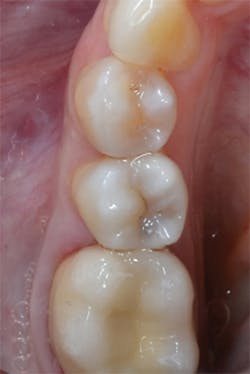

Figure 11: Preoperative view of teeth Nos. 4 and 5. The treatment plan includes composite restorations.

Figure 12: Final preparations on teeth Nos. 4 and 5. The Palodent Plus Sectional Matrix System has been used to isolate the MOD prep on tooth No. 4 and MO prep on tooth No. 5. The Palodent Plus Sectional Matrix System can be configured to restore multiple surfaces and multiple teeth in the same quadrant.